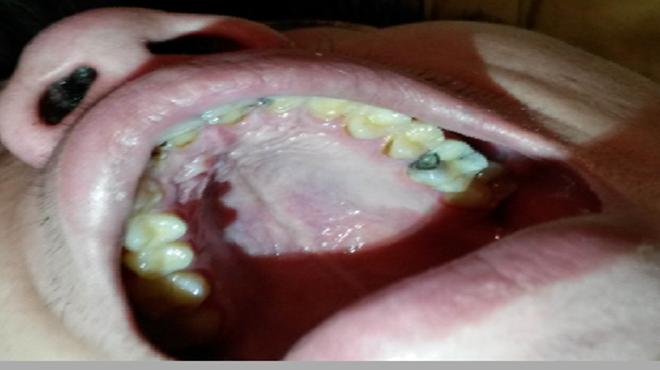

很多人因为常吃甜食或是过于刺激的食物,而没有及时刷牙,又或是晚上没有养成刷牙的好习惯,时间久了导致口腔内细菌的滋长,就可能诱发牙齿疾病。一般蛀牙就是这样生成的,牙齿表面出现黑色的小洞,若任其发展,小洞就会越来越大,吃饭塞牙,最终疼痛难忍。

蛀牙会带来疼痛,平时可能没啥感觉,但是只要一吃食物牙齿就会疼的厉害,久而久之就会造成偏嚼的习惯,让整个面部看起来都不协调,而且蛀牙如果发生在前牙,张口就是一个黑洞,那该多难看啊。